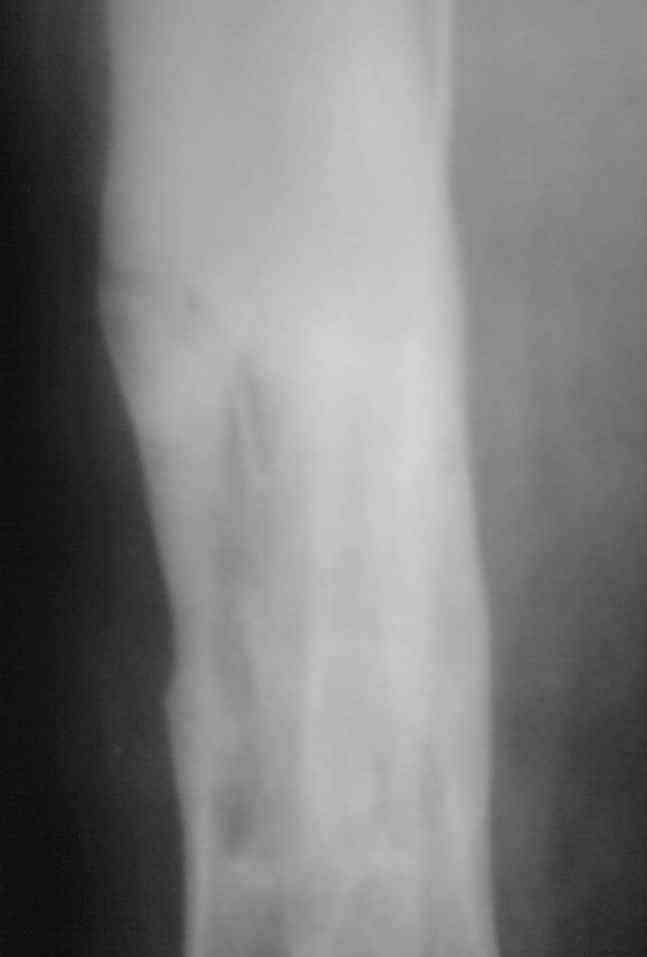

Здравствуйте коллеги! Прошу помочь с лечением больного. Мужчина в полном расцвете сил в апреле 2004 года получил травму - открытый оскольчатый перелом голени. Через 2 дня произведён МОС большеберцовой кости пластиной АО и винтами. Послеоперационный период осложнился остеомиелитом. Через 3.5 месяца пластина удалена. В марте 2005 года оперативное лечение в г. Екатеринбурге - санирование очага, некрэктомия. В июне 2006 года в ОКБ произведена секвестрэктомия, через неделю некрэктомия. Неоднократно получал антибактериальную терапию, в результате чего сформировалась сенсибилизация ко многим антибактериальным препаратам. В данный получает перевязки. Локально сохраняется кратерообразная гнойная рана, размерами до 4 х 3 см. Хотелось бы узнать Ваши мнения по поводу дальнейшего ведения данного пациента.

Выкладываю снимки в хронологическом порядке. Снмки все какие есть у больного.

Количество не заменяет качества, поэтому не стоит выкладывать весь хлам, какой удастся найти у пациента. Лучше сделать 1)свежие 2)хорошего качества рентгенограммы, чтобы оценивать ситуацию по ним, а не по мутным огрызкам.